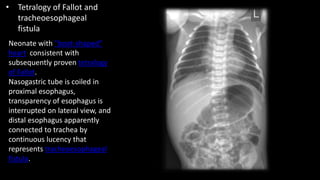

• Tetralogy of Fallot and

tracheoesophageal

fistula

Neonate with "boot-shaped"

heart consistent with

subsequently proven tetralogy

of Fallot.

Nasogastric tube is coiled in

proximal esophagus,

transparency of esophagus is

interrupted on lateral view, and

distal esophagus apparently

connected to trachea by

continuous lucency that

represents tracheoesophageal

fistula.